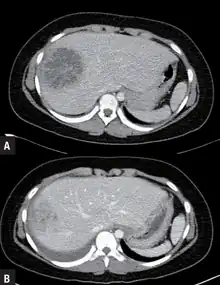

- USG and CT scanning